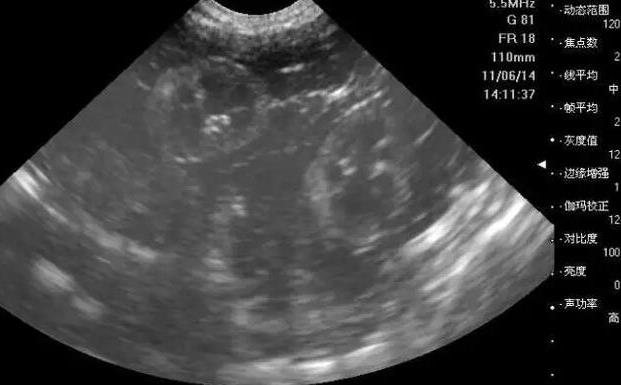

苏州试管供卵 苏州第三代试管婴儿医生、专家怎么选择? ‘30周b超单看男女的方法’